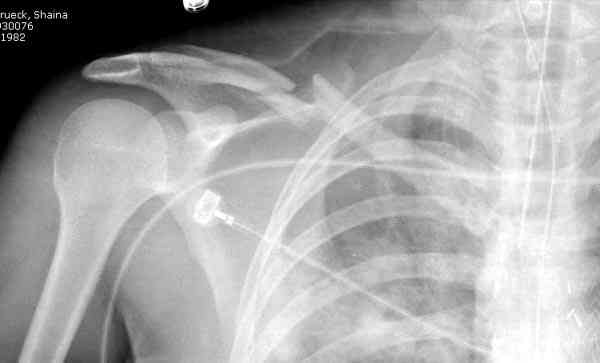

Судя по проекциям ключицы, очевидно разобщение фрагментов, чаще всего сопровождающееся интерпозицией платизмой. для 15 летнего пациента, категории физически активных пациентов выбрал бы оперативный метод( интрамедуллярно

винтом с частичной резьбой).

Спицы противопоказаны не только из-за отсутствия стабильности, также из-за их опасной миграции. Описаны много случаев миграции спиц даже в каротидную артерию.